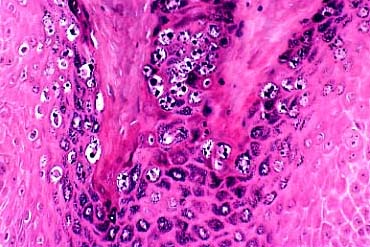

Verruca vulgaris = الثؤلول الشائع